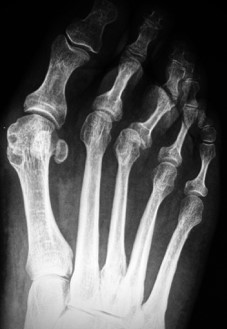

Para evitar la aparición de metatarsalgias de transferencia, la osteotomía no solo se realizó en el metatarsiano correspondiente a la hiperqueratosis. En el caso de una hiperqueratosis plantar bajo la cabeza de M2 se realizaron osteotomías en el M2 y M3. Ante la hiperqueratosis plantar bajo la cabeza de M3 se realizaron osteotomías en M2, M3 y M4. Para la hiperqueratosis plantar bajo la cabeza de M4 se realizaron osteotomías en M3 y M4 [6]. Las osteotomías estaban indicadas en los tres metatarsianos centrales excepto en casos excepcionales de hiperpresión en la cabeza de un único metatarsiano, habitualmente M4, correspondiente a metatarsalgia por descenso del metatarsiano. Utilizamos fluoroscopia para determinar la orientación de la osteotomía, un ángulo de 45° con el plano del suelo, realizando supinación con la mano para evitar cambiar la dirección del corte (Figura 1).

Figura 1a

Figura 1b

Al mes se programó una radiografía y si había suficiente callo fibroso se le dio la opción a la paciente de usar otro tipo de zapato, pero siempre de suela ancha y dura (Figura 3).

Figura 3a

Figura 3b

Del estudio radiográfico solo 8 pies cambiaron a Plus (M1>M2), de esos 5 fueron Plus minus (M1=M2) y tres Minus (M1<M2) antes de la cirugía (Figura 5).

En nuestro estudio cambiaron, después de la cirugía DMMO, su fórmula metatarsal ocho pies que eran Plus (M1>M2), 5 se transformaron en Plus minus (M1=M2) y tres en Minus (M1<M2).

Figura 1. Evolución radiográfica de metatarsalgia aislada, radiografía dorso – plantar a) preoperatoria, b) postoperatoria, c) al año de la intervención

Figura 4. Evolución radiográfica de metatarsalgia asociada a hallux valgas tratada con técnica de Reverdin-Isham, radiografía dorso – plantar a) preoperatoria, b) postoperatoria, c) al año de la intervención

Figura 5. Fórmula metatarsal radiográfica global, en ambos grupos, antes y después de la cirugía